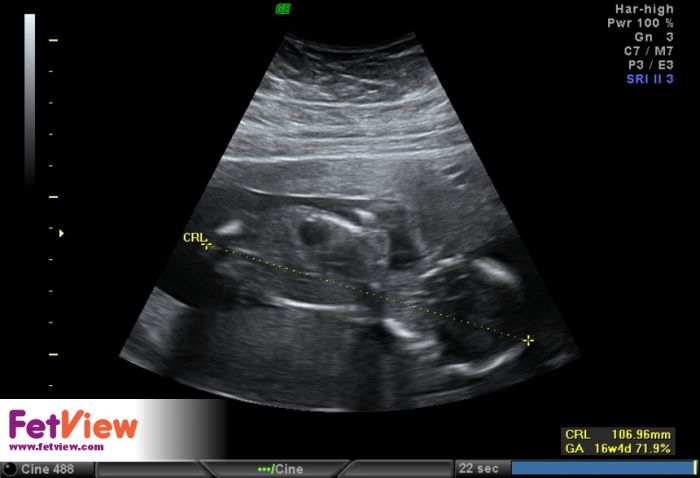

Ahojky, tak sse hlásím po kontrolách, včera jsme byla u svého doktora a vše ok, jen maličká nechtěla moc spolupracovat pořád na nás vystrkovala záda asi se styděla :-) takže zkontroloval co se dalo, chtěl udělat i foto 3d ale nebylo fakt nic vydět :-( takže snad příště, máme skoro 11cm .-) fotečky přikládám. U genetičk taky vše v pořádku i ostatní výsledky po odběru klků ok, tak se mi ulevilo. No a dneska jsme byla u Apolináře na kontrole po tom odběru, udělali mi podrobný ultrazvuk a tak jsme viděla všechno - hlavu, oči, žaludek, pusu, ruce i s kostičkama, močový měchýř...tý jo koukla jsme jak divá :-) doktor byl super všechno mi vysvětlil a popsal a moc hezky jsme si i popovídali :-)

já jsem dnes taky po kontrole,prvek ma 10cm a ukázal i pindika